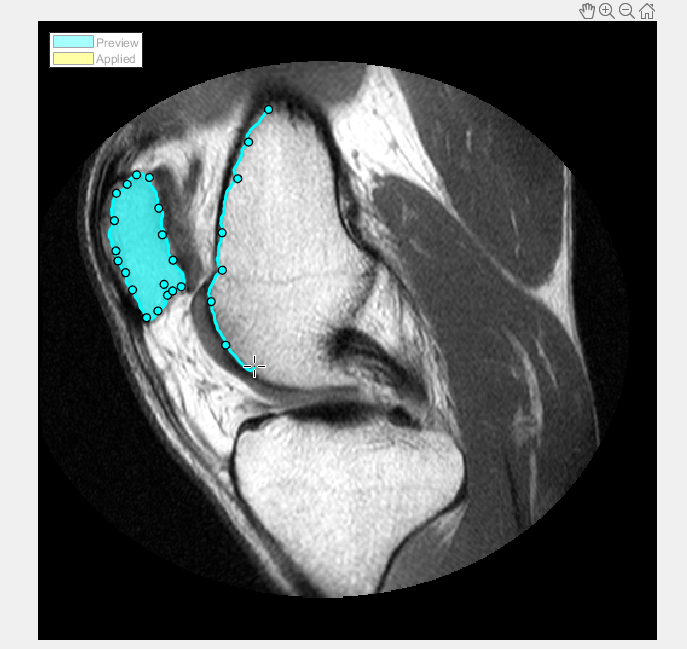

В данном примере считайте изображение в рабочую область. Этот пример использует изображение MRI колена. Цель состоит в том, чтобы создать рисунок маски, который сегментирует кость от мягкой ткани в изображении.

Выберите тип ROI, который вы хотите чертить. В данном примере выберите Assisted Freehand. Когда вы перемещаете курсор через изображение, он превращается в форму креста нитей. Нажмите кнопку мыши и начните чертить форму от руки по области изображения, которое вы хотите сегментировать. С опцией ROI От руки, которой Помогают, которая предварительно выобрана, можно чертить форму от руки, которая автоматически следует за ребрами в основном изображении, чтобы помочь вам чертить более точный ROI. Как вы чертите, щелкаете мышью, чтобы создать waypoints. Waypoints может помочь вам внести точные корректировки в форму после того, как вы закончите чертить. Чтобы добавить дополнительный waypoints после того, как вы закончите чертить, дважды кликните на ребре ROI.

Продолжите чертить формы до всех областей, которые вы хотите сегментировать, идентифицированы. Чтобы сохранить области ваш чертили, нажмите Apply (их цветные изменения в желтом). Чтобы возвратиться к вкладке Segmentation, нажмите Close ROI.